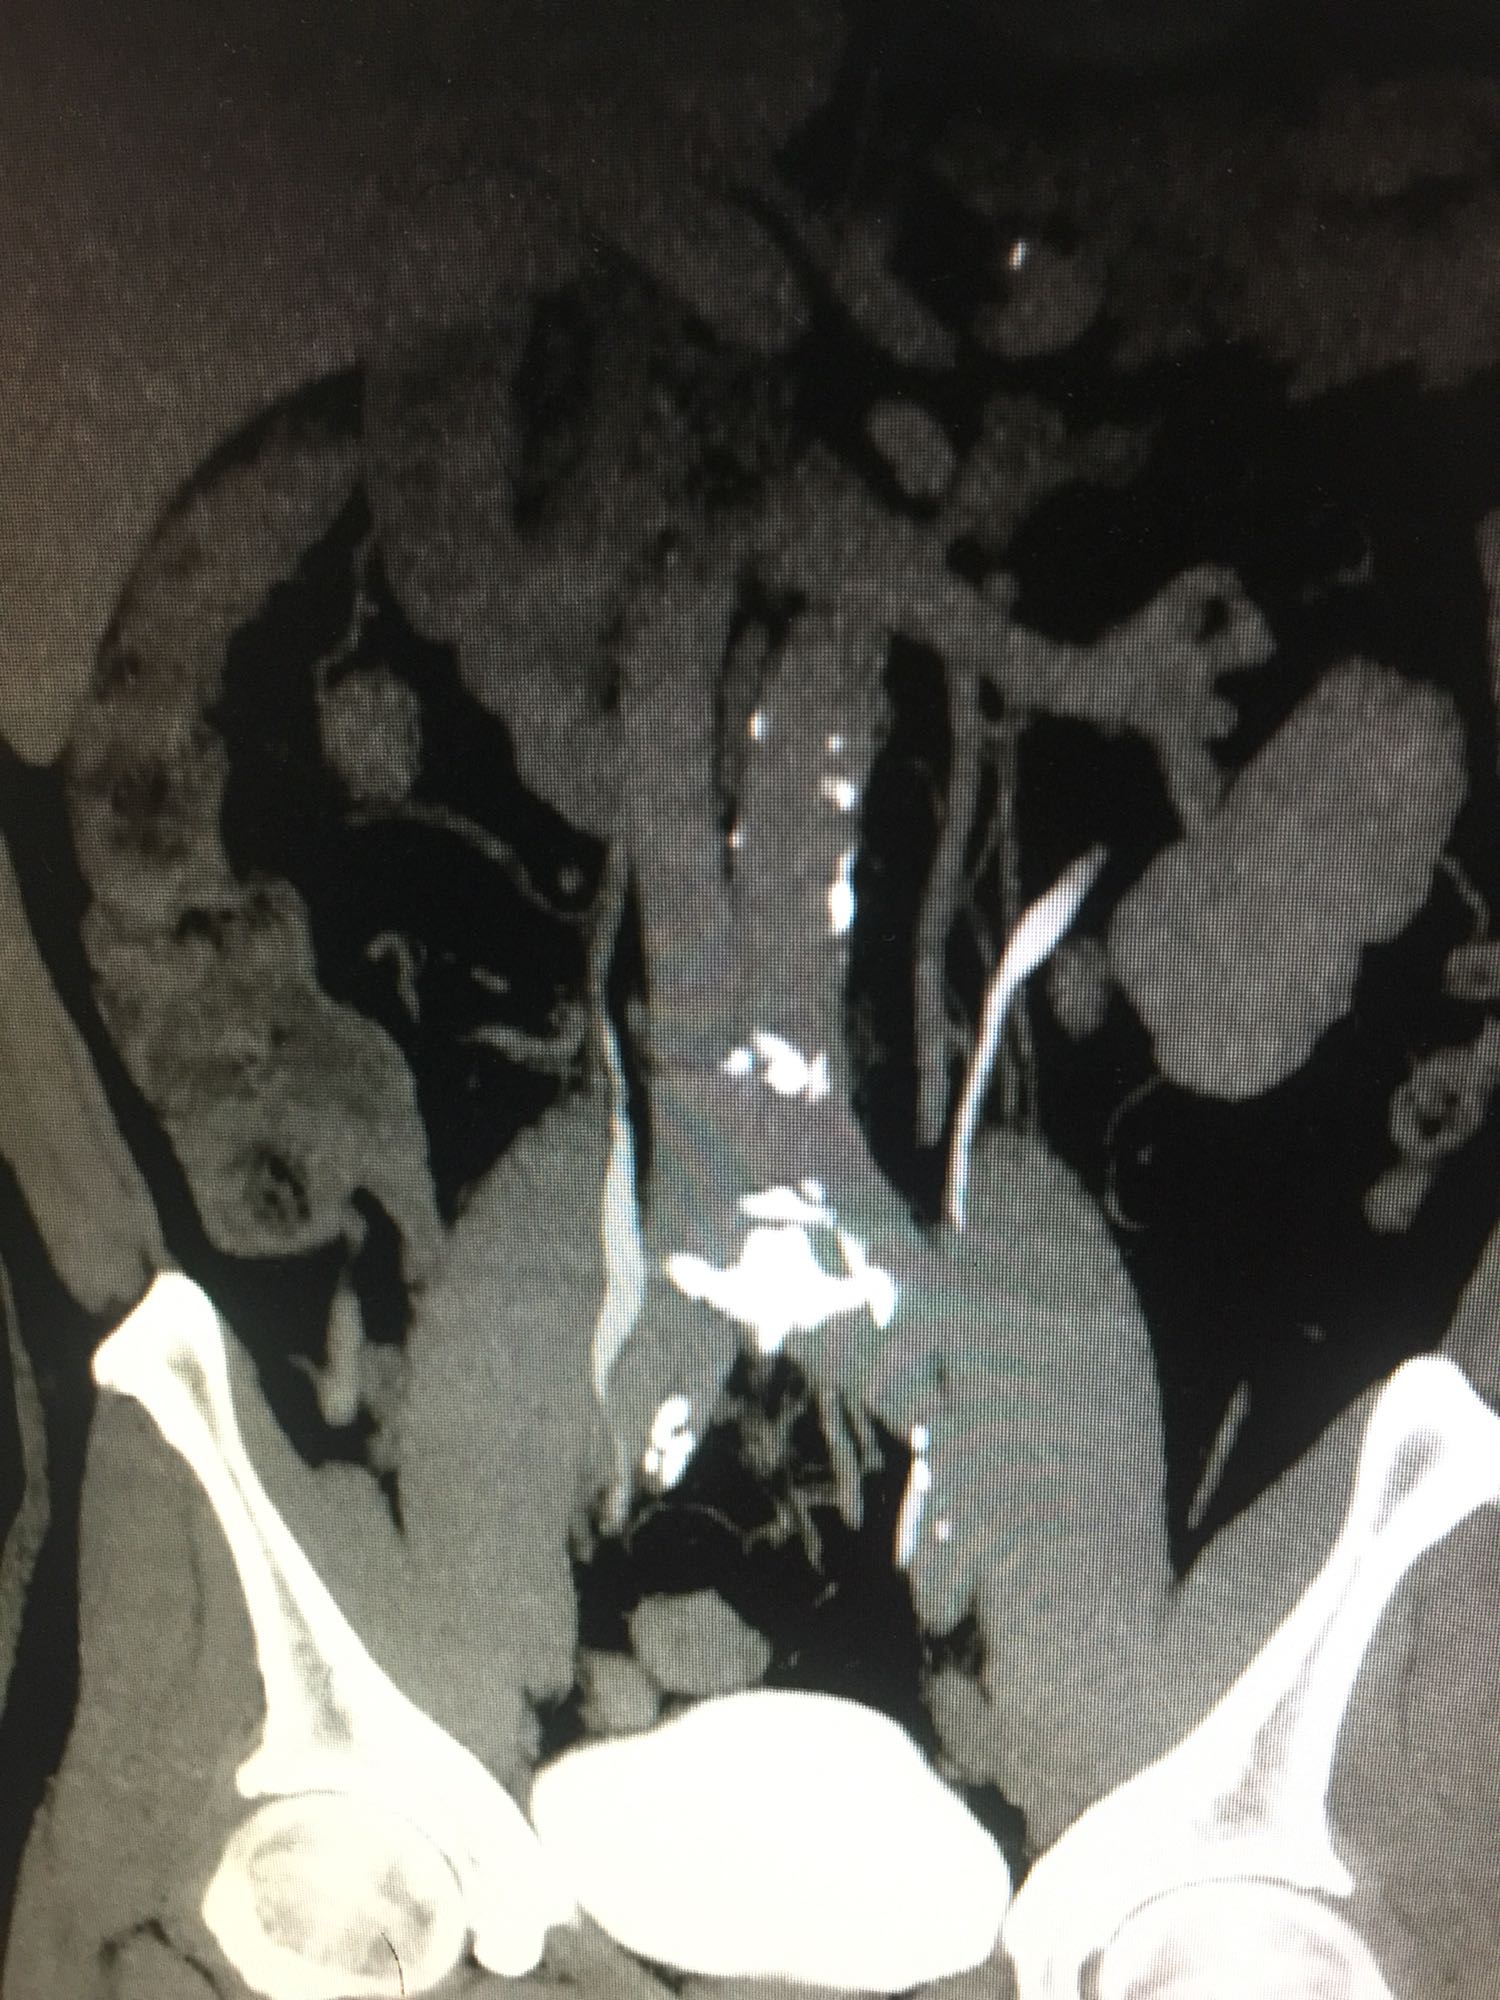

查体:双肾区无叩压痛,膀胱区无叩压痛,无叩浊,前列腺二度,质地中等,无压痛,无结节。CTU提示右肾铸型结石。ECTL 40,R14.5

右肾铸型结石 予以经皮肾碎石治疗,术后复查平片未见结石残留。

铸型结石以经皮肾手术作为主要的术式。但手术可能一次或多次进行。术后残留结石,术后复发等几率高。我们见过2月后几乎又长满的结石。